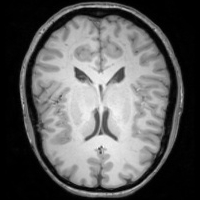

4.4 Qualitative Evaluation

In Figure 5 we analyze the prediction quality of our and compared approaches in a qualitative way. Considering modality propagation in MRI, we see that usage of uncertainty-aware patch invariance (UAPI) gives a better detailed weighting of the cerebrospinal fluid in the middle of the brain. In general, employing patch invariance yields better preservation of fine structures. This observation also applies to accelerated MRI enhancement. In particular, CUT and UAPI provide comparatively sharper knee images with more high-frequency details than the other methods.